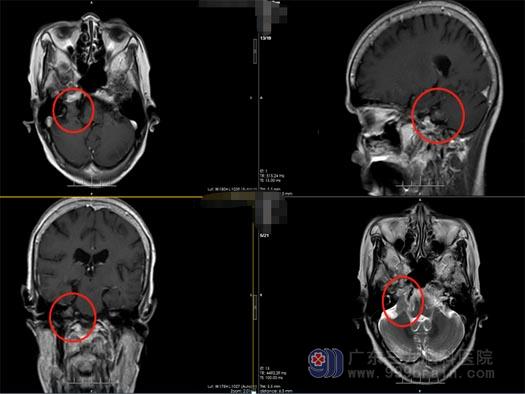

焦灼不安的家人带着李婆婆来到了广东三九脑科医院神经外五科,进一步MRI+C检查提示:右侧桥小脑角区占位性病变,考虑为神经鞘瘤。

李婆婆的颅内占位效应明显,有颅神经损害的症状,神经外五科治疗团队建议手术治疗,李婆婆和家人也非常赞同治疗方案。经过周密的准备,治疗团队为李婆婆施行了“右侧桥小脑角区神经鞘瘤切除术”,术中见肿瘤位于右侧桥小脑角,黄白色,质中,予显微镜下电凝分块切除,右侧前庭神经位于肿瘤下方、面神经位于肿瘤上方,经分离面神经保留完整,三叉神经、舌咽神经受肿瘤压迫明显,经细心分离完整保留,肿瘤于显微镜下全切,右侧内听道肿瘤给予反复电凝烧灼,术腔止血彻底。